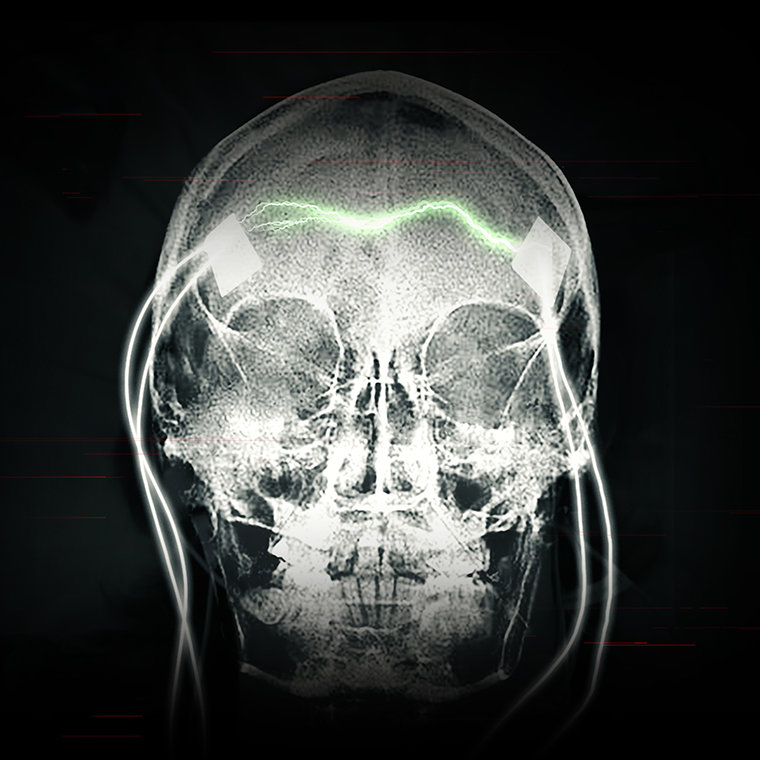

Heute attackieren Psychiater das Gehirn regelmäßig mit viel mehr Elektrizität als früher, um einen Krampfanfall hervorzurufen.

Das Ergebnis bleibt das gleiche: ein Grand mal Anfall und Gehirnschäden, die dauerhaft sein können. Der enorm gesteigerte Stromfluss, der heute benutzt wird, kann Löcher in Gehirnzellen reißen und die Zellen töten. Der Strom kann die Zellen auch durch Wärmeerzeugung töten. MRTs von EKT-Patienten haben Vernarbung und Hirnschrumpfung gezeigt – eindeutige Anzeichen schwerer Schäden.